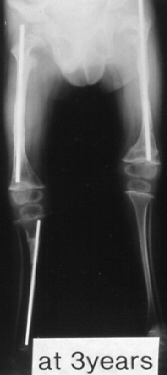

Case 3.

A 14-years-old boy. Body height 124 cm. Sillence type sporadic.

The first visit was at 2 years-old. He sustained one fracture in U/E and 8 fractures in L/E, underwent 10 operations, and has 60 degrees scoliosis. He became able to walk on crutches at 2 years old and had been a practical ambulator until 12 years old. He sustained a fracture at the distal end of right femur where an intramedullaly nail did not reached. He uses a wheelchair for long distant transportation. This case is supposed to be on the border line between ambulator and non-ambulator. The diameter of the femur was 10 mm at 3 years of age and 11mm at 13 years of age. No increase of diameter has been observed despite rather thin intramedullaly nailing.